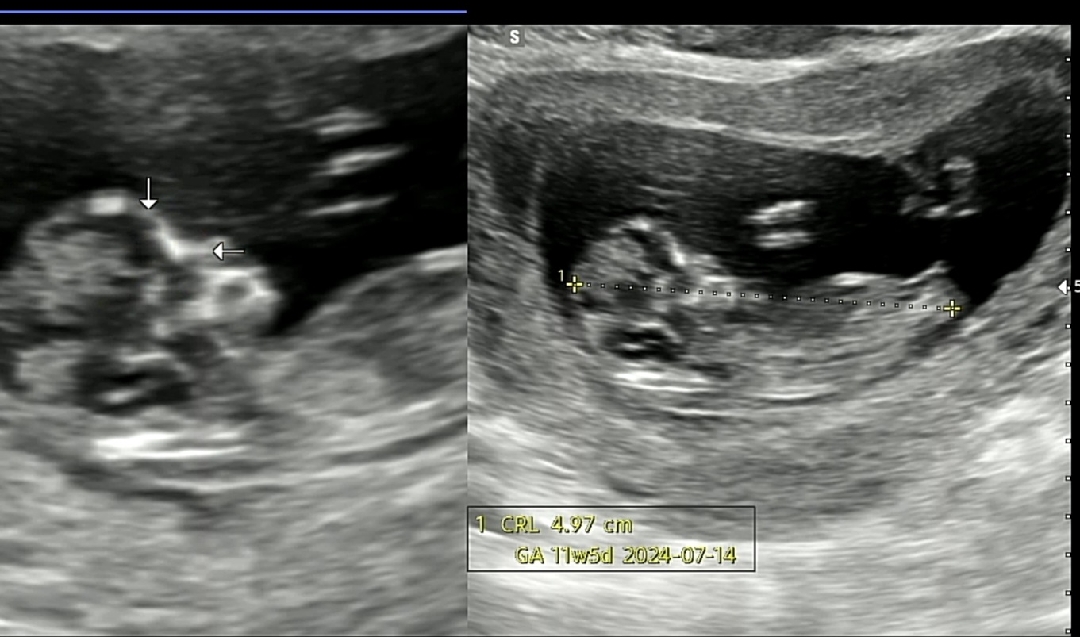

12주 초음파 각도법

쪼기 다리쪽에 보이는게 생식기일까요? 담주에 병원가는데 성별 너무 궁금해요😭😭 각도법으로 보시기에 딸일까요 아들일까요?!